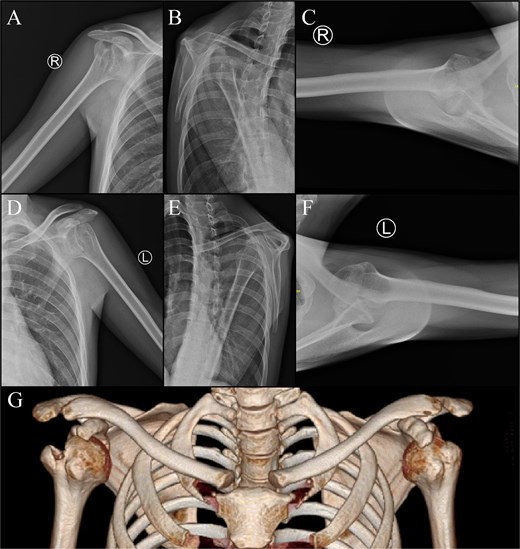

Physical examination was conducted. The deltoid contour was lost on the right and left shoulder. There was no swelling, bruising, wound, or scar found. Neurovascular test on the distal part of both shoulders indicates intact structures. Limitation of shoulder range of motion (ROM) was noted (Fig. 1). Plain radiographs and CT scan (Fig. 2) showed a bilateral anterior dislocation of the glenohumeral joint with GT fracture.

Imaging of the right shoulder : (A) anteroposterior view; (B) scapular Y view; (C) axillary view. Imaging of the left shoulder : (D) anteroposterior view, (E) scapular Y view, (F) axillary view. (G) 3D computed tomography scan.